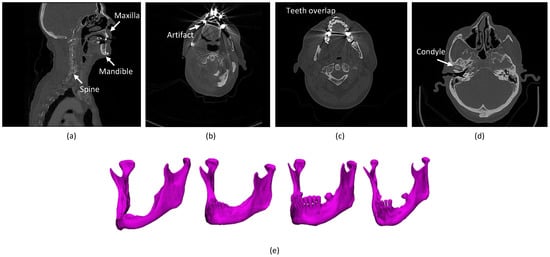

- The presence of anatomically complex bony structures in the scans. As the examples show in Figure 1a, a normal H&N scan includes other bony structures, with a complex anatomy and a similar density. Determining the correct boundaries and separating the mandibular bone from the other bones may be challenging.

- Artifacts. When X-rays pass through high-density structures or materials, including teeth, postoperative metal implants, etc., the signal on the detectors will change, which will lead to attenuation calculation errors in the (cone beam) computed tomography (CBCT/CT) reconstruction process and consequently cause high noise and strong artifacts in the visual impression of the scans [16]. The mandible boundaries nearby teeth tend to be blurred and hard to detect. In particular, the boundaries of mandible rami are difficult to be identified when dental braces and metal implants badly affect the image quality [17], as shown in Figure 1b. Furthermore, the fact that the superior and the inferior teeth are at the same slice and even overlapping that makes segmentation methods challenging, as shown in Figure 1c.